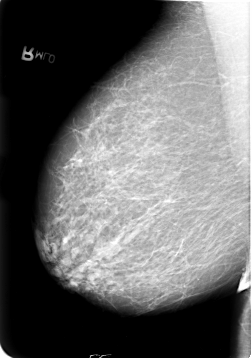

B_3021_1.RIGHT_MLO

ics_version 1.0

filename B-3021-1

DATE_OF_STUDY 13 9 1994

PATIENT_AGE 59

FILM_TYPE REGULAR

DENSITY 3

DATE_DIGITIZED 2 7 1997

DIGITIZER LUMISYS LASER

RIGHT_MLO LINES 5720 PIXELS_PER_LINE 4024 BITS_PER_PIXEL 12 RESOLUTION 50 NON_OVERLAY